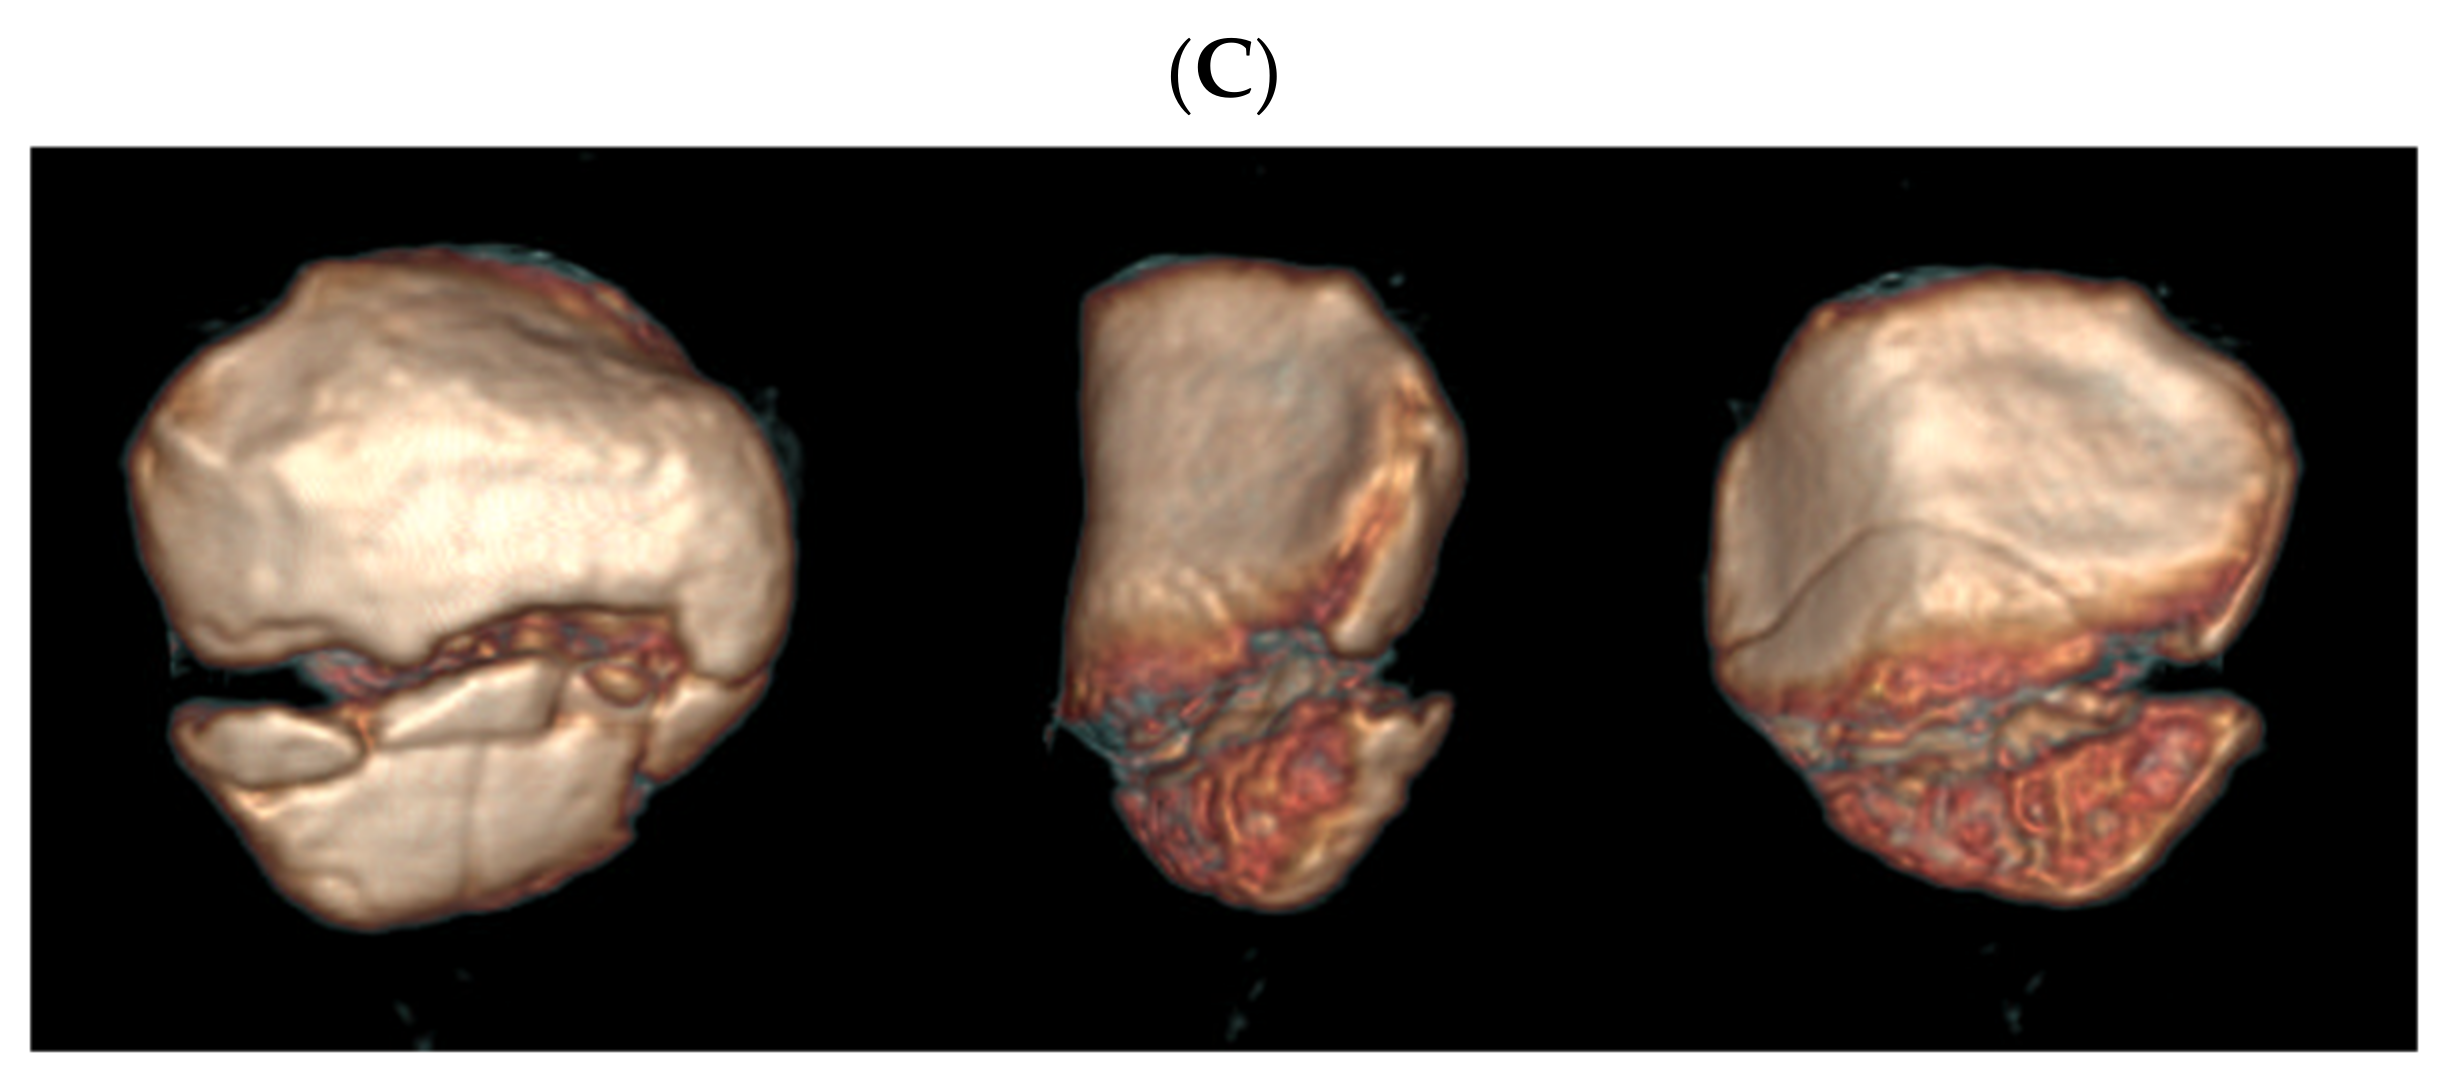

Figure 3. Plain radiographs (A), two-dimensional computed tomography (B), and three-dimensional computed tomography (C) of a patellar inferior pole fracture. In addition to the displaced extra-articular fracture, non-displaced linear articular fracture lines exist. The respondents chose either type A or C.